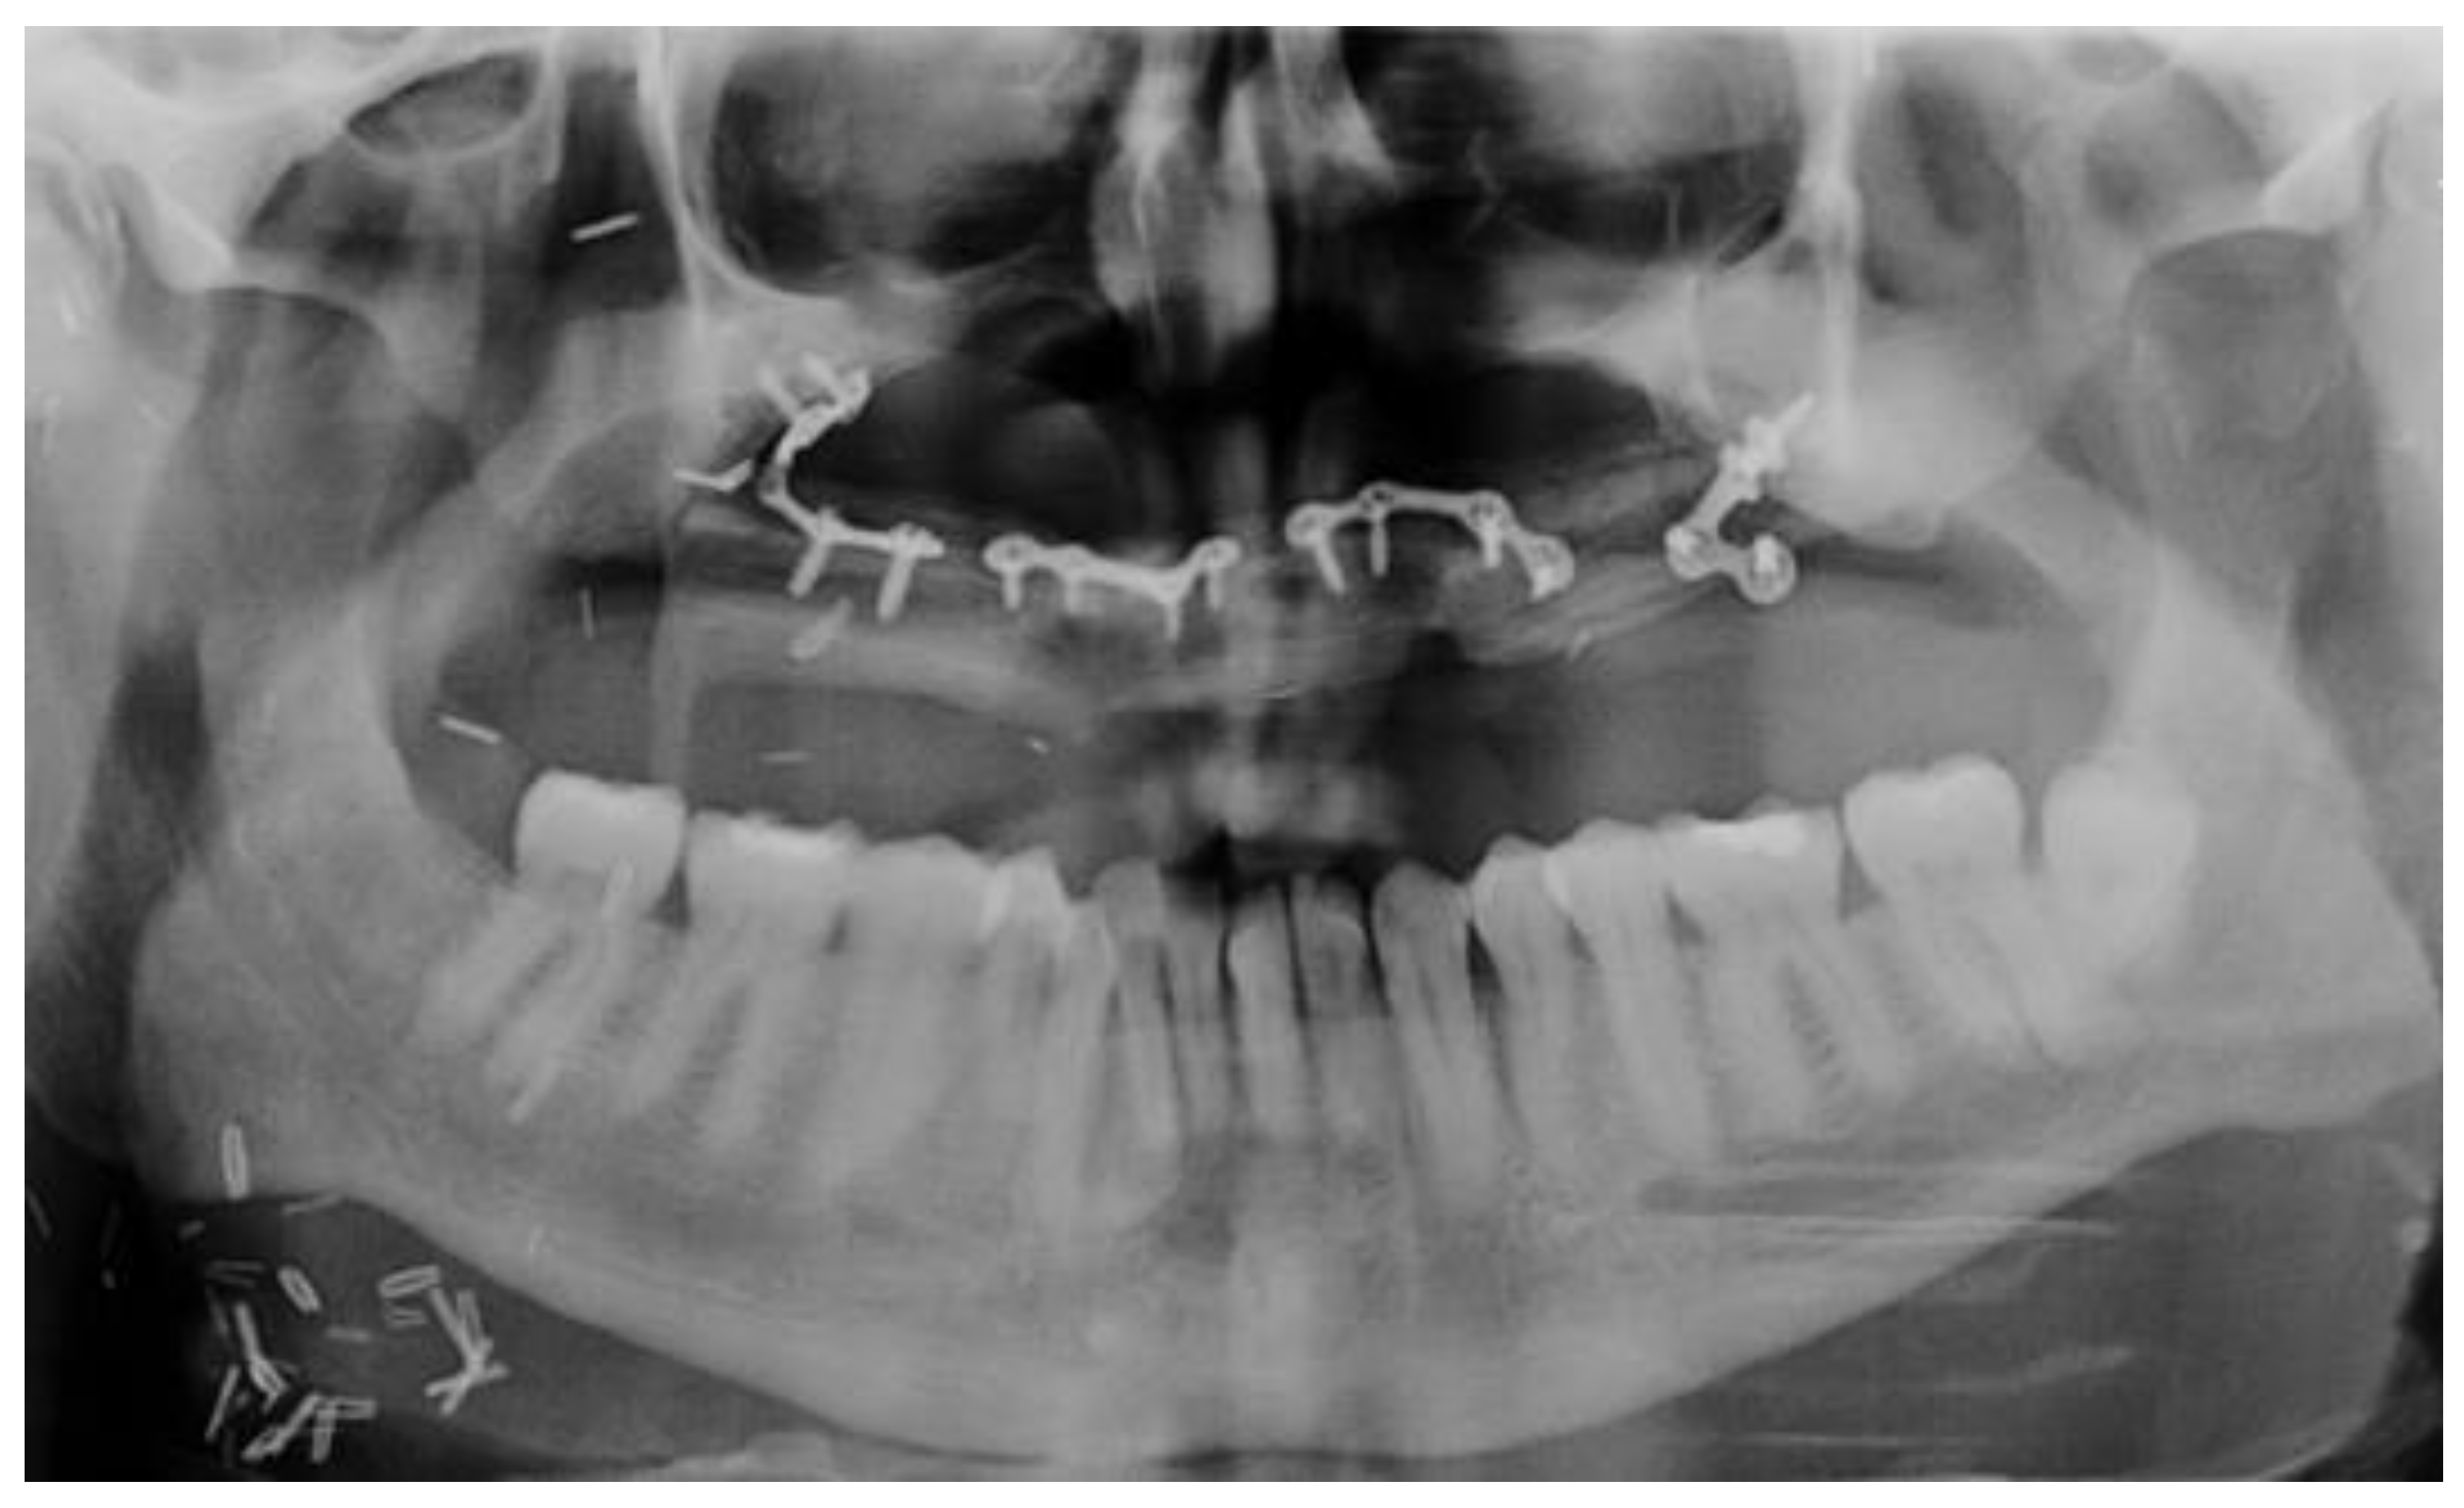

- Bone tissue condition: insufficient bone volume, the impossibility of bone augmentation for implant insertion, presence of jaw plates.

- Brauner, E.; Di Carlo, S.; Ciolfi, A.; Pompa, G.; Jamshir, S.; De Angelis, F.; Della Monaca, M.; Valentini, V. Use of Porous Implants for the Prosthetic Rehabilitation of Fibula Free Flap Reconstructed Patients. J. Craniofac. Surg. 2019, 30, 1163–1169. [Google Scholar] [CrossRef]

- Zavattero, E.; Ramieri, G.; Agrò, G.; Fasolis, M.; Garzino-Demo, P.; Borbon, C. Implant Dental Rehabilitation of Fibula-Free Flap Reconstructed Jaws. J. Craniofacial Surg. 2021, 32, e134–e136. [Google Scholar] [CrossRef] [PubMed]

- Brauner, E.; Quarato, A.; De Angelis, F.; Pompa, G.; Jamshir, S.; Valentini, V.; Di Carlo, S. Prosthetic rehabilitation involving the use of implants following a fibula free flap reconstruction in the treatment of Osteosarcoma of the maxilla: A case report. Clin. Ter. 2017, 168, e392–e396. [Google Scholar] [CrossRef]

- Papi, P.; Brauner, E.; Di Carlo, S.; Musio, D.; Tombolini, M.; De Angelis, F.; Valentini, V.; Tombolini, V.; Polimeni, A.; Pompa, G. Crestal bone loss around dental implants placed in head and neck cancer patients treated with different radiotherapy techniques: A prospective cohort study. Int. J. Oral Maxillofac. Surg. 2019, 48, 691–696. [Google Scholar] [CrossRef]